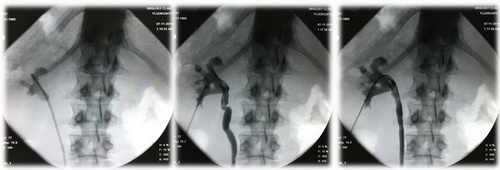

Рис. Рентгенологические этапы операции.

Реальный кейс: чрескожная нефролитотрипсия пациентке 28 лет при коралловидном камне

Операция: Чрескожная нефролитотрипсия.

Хирург: доктор медицинских наук Акопян Г.Н.